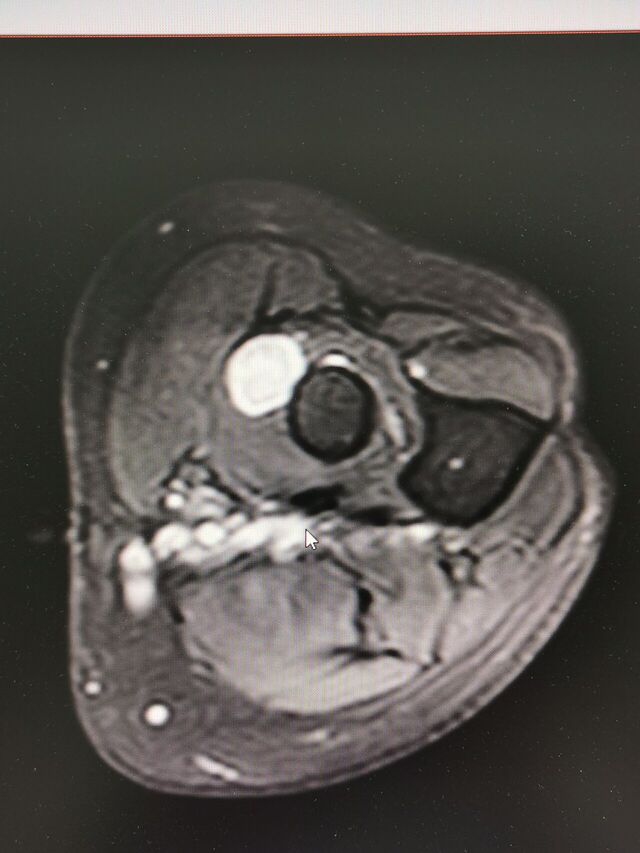

复习断层解剖: